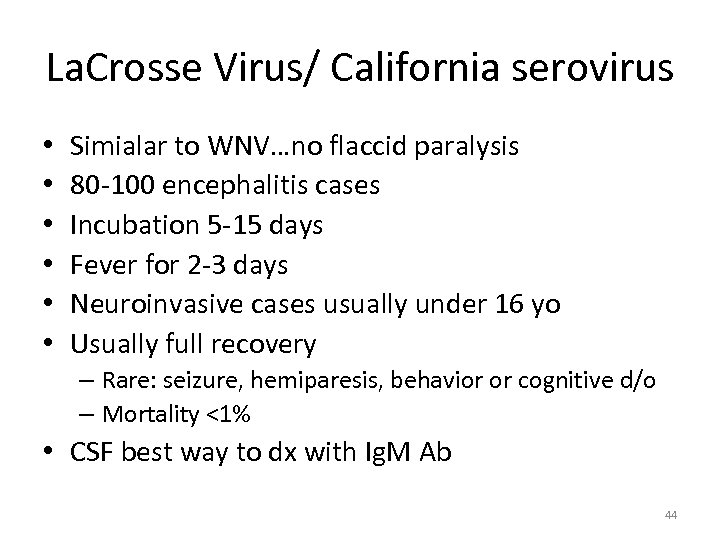

La. Crosse Virus/ California serovirus • • • Simialar to WNV…no flaccid paralysis 80 -100 encephalitis cases Incubation 5 -15 days Fever for 2 -3 days Neuroinvasive cases usually under 16 yo Usually full recovery – Rare: seizure, hemiparesis, behavior or cognitive d/o – Mortality <1% • CSF best way to dx with Ig. M Ab 44